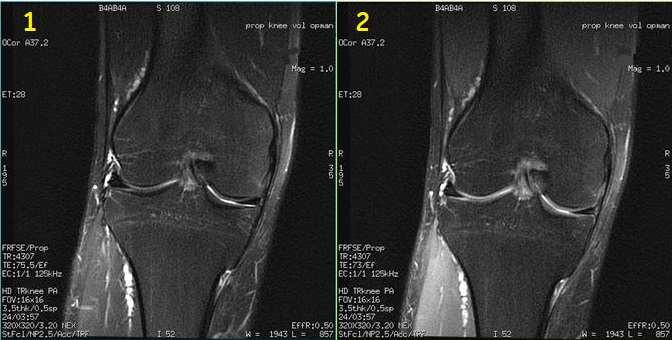

Modify the flip angle to produce increased signal from cartilage. Typically use a 80° flip angle. Figure 5. Two PROPELLER images comparing cartilage signal intensity

Table 5. Image legend

Number

Description

1

160° flip angle

2

80° flip angle that demonstrates increased signal from cartilage